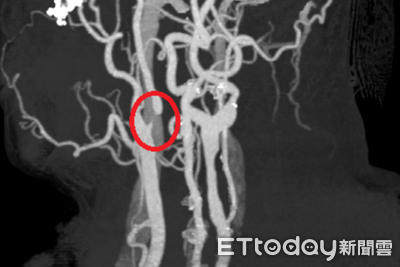

50歲林姓男子近日因不時感到頭暈、左邊手腳麻而就醫檢查,經神經內科醫師初步安排電腦斷層檢查,雖未發現明顯中風跡象,但基於臨床警覺,進一步安排頸動脈超音波檢查,結果發現內頸動脈已有狹窄情形,隨即收治住院觀察,並轉介神經外科醫師接受內頸動脈血管成形術(氣球擴張合併支架置放),成功改善腦部血流,術後恢復良好、已康復出院。 《詳全文...》